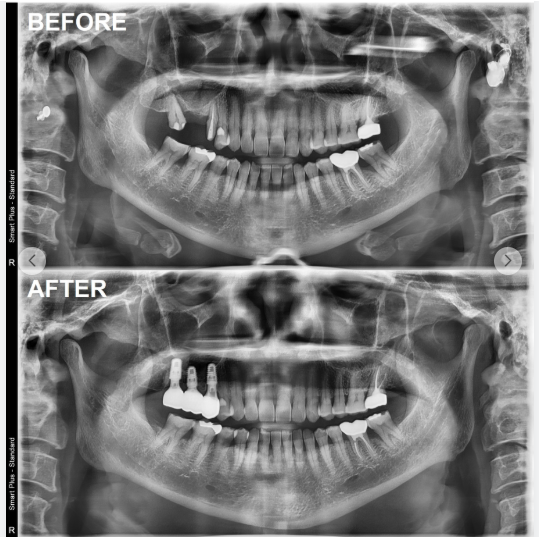

(영구치 결손 임플란트 치료 사례)

다음으로 중요한 것은 나와 비슷한 치료 사례가 있는지 확인하는 것입니다.

"앞니가 빠진 경우",

"어금니 여러 개가 없는 경우",

"뼈가 많이 부족한 경우" 등

자신과 유사한 상황의 치료 과정과 결과를 사진이나 영상으로 설명해주는지 살펴볼 필요가 있습니다.